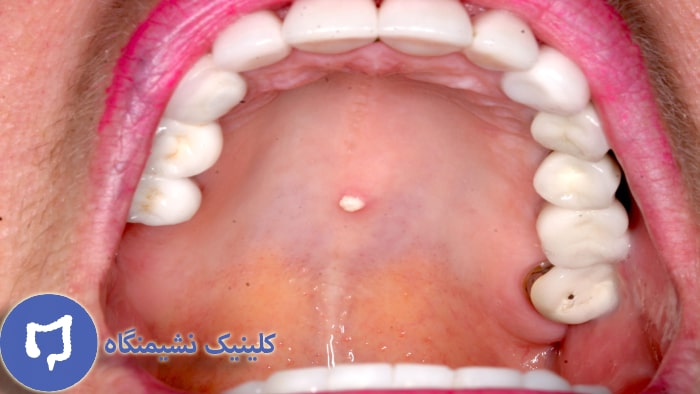

برخی افراد این سوال برایشان پیش می آید که زگیل روی لب چه شکلی است؟ یا حتی زگیل دهان موجب چگونه است؟ با مشاهده عکس زگیل روی زبان و دهان می توانید به طور کامل با آن آشنا شوید.

در ادامه به چندین نمونه از تصویر زگیل تناسلی در دهان اشاره خواهیم نمود تا با مقایسه آنان به تفاوتشان پی ببرید.

تصویری که مشاهده می کنید، نمونه ای از زگیل دهانی است که در صورت عدم درمان و جلوگیری از آن موجب گسترش آن شده و درمان آن دشوار می گردد. علاوه بر آن می توانید با مشاهده نمونه هایی از عکس زگیل تناسلی در نقاط مختلف بدن به نوع دقیق این بیماری پی ببرید.